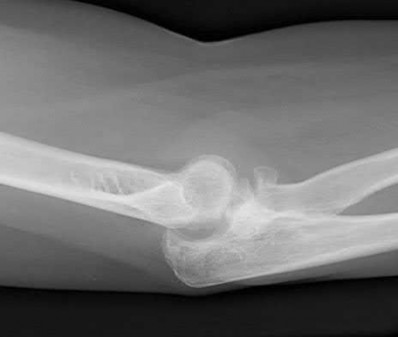

A 24-year-old woman is thrown from her motorcycle and sustains the closed injury shown in Figures A through C. Open reduction and internal fixation is planned. What surgical technique will best allow visualization of the joint surface and allow early range of motion?

Access to complex intra-articular fractures is best achieved by an olecranon osteotomy (OO). Fixation can be with parallel plating or orthogonal plating.

Bicolumnar fixation of distal humerus fractures should follow the principles outlined by O'Driscoll: Distal fragments should be held by as many screws as possible; every screw in the distal fragments should pass through a plate; each screw should engage as many articular fragments as possible.

Galano et al. review treatment for bicolumnar distal humerus fractures. They note that the olecranon osteotomy, Alonso-Llames triceps sparing and Campbell triceps splitting approaches expose 57%, 46% and 35% of the articular surface, respectively. The OO and paratricipital (triceps sparing)

approaches allow for early ROM. Protected motion is required for the O'Driscoll TRAP and Bryan-Morrey approaches for tendon-to-bone healing.

Coles et al. retrospectively reviewed the OO in fixation of 70 fractures. Osteotomy fixation was with an intramedullary screw and dorsal ulnar wiring, or with a plate. The rate of OO increased with fracture difficulty (from AO type C1-C3). There was 1 delayed union but no nonunions.

Figures A and B show a AO/OTA type C2 intraarticular distal humerus fracture. Figure C is a coronal CT scan showing intraarticular comminution. Illustration A shows fixation of the fracture with bicolumnar plating through an olecranon osteotomy approach. Illustration B shows the various approaches to the distal humerus (left, Campbell triceps splitting; center left, O'Driscoll triceps reflecting anconeus pedicle; center right, Bryan-Morrey approach, leaving the triceps attached laterally to the fasciocutaneous flap, but elevating it off the ulna; right, olecranon osteotomy). Illustration C shows 3 methods of olecranon osteotomy (A and B, Intra-articular transverse; C-F, Extra-articular oblique; G, Intra-articular chevron).

Incorrect Answers:

Answer 1: The Bryan-Morrey approach provides excellent medial exposure, but inadequate lateral exposure. The triceps is lifted subperiosteally, and the anconeus is released subperiosteally. Triceps repair depends on tendon-bone healing.

Answer 2: The O'Driscoll TRAP approach detaches triceps and anconeus from their distal insertions in a V-shaped flap that is reflected proximally. Repair to bone is via drill holes in the ulna. Early mobilization is not recommended.

Answers 3 and 5: Orthogonal plating is performed on the POSTEROLATERAL and MEDIAL surfaces.